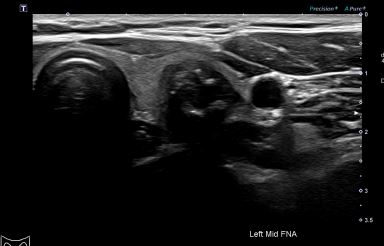

상기환자 갑상선 외부검사상 이상소견으로 세침검사하신 30대 여성분으로

의심스러운 갑상선 좌엽 검사 결과 갑상선암으로 진단되었습니다